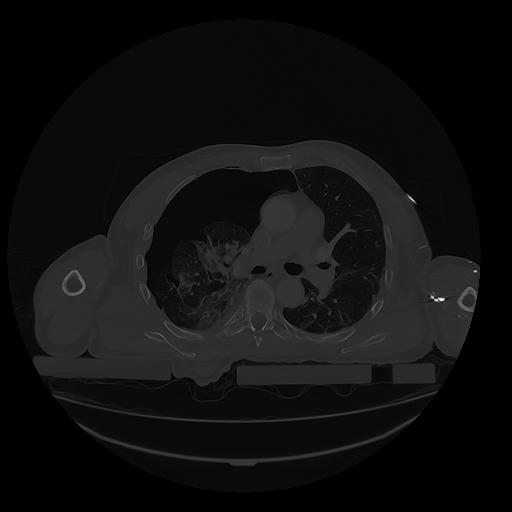

31 PULMON,CE,Vol,1.0,PULMON,,